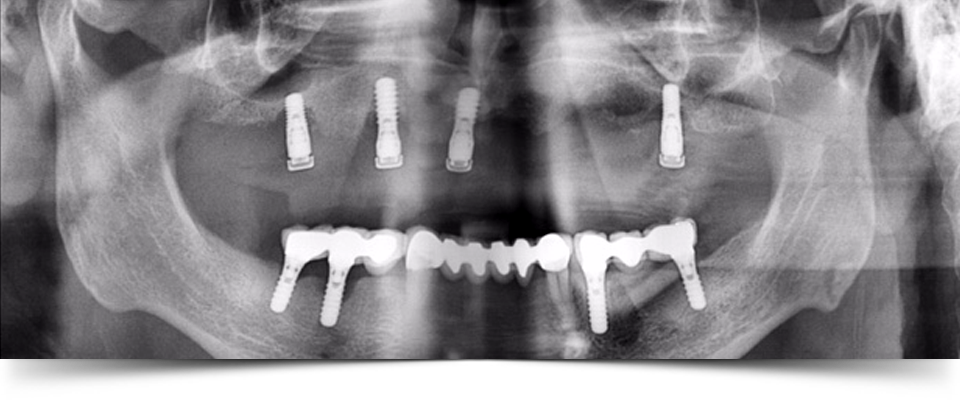

LOS IMPLANTES son la solución ideal para la sustitución de dientes perdidos, ya se trate de una pérdida parcial o completa de ellos. A veces es necesario realizar algún tipo de cirugía previa para su posterior colocación, como la elevación de seno o el ingerto óseo.